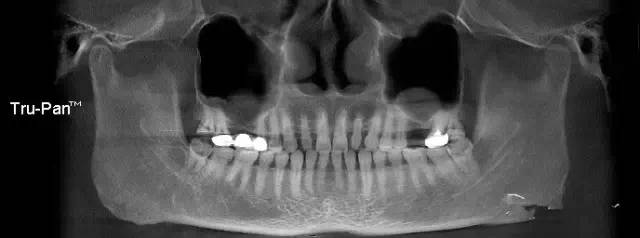

第二圖:上頜竇氣化,導(dǎo)致上頜竇很大,骨高度不足,但是上頜竇底平,粘膜很干凈。適合外提升或者高手可行內(nèi)提升。(還有二次內(nèi)提升)。